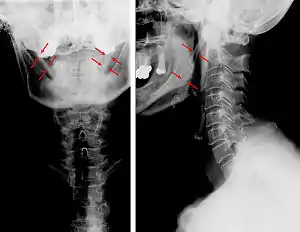

| Anteroposterior and lateral radiographs of cervical spine showing ossification of the stylohyoid ligament on both sides | |

Radiograph, lateral view showing elongated stylohyoid process and stylohyoid ligament ossification

Radiograph, lateral view showing joint-like formation in ossified stylohyoid ligament